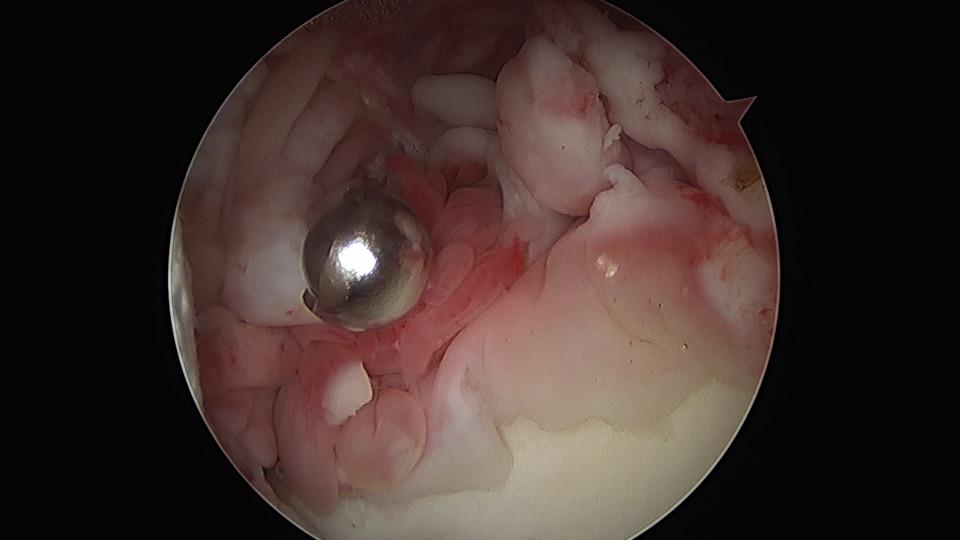

这是滑膜软骨瘤病

膝关节滑膜软骨瘤病

滑膜骨软骨瘤病